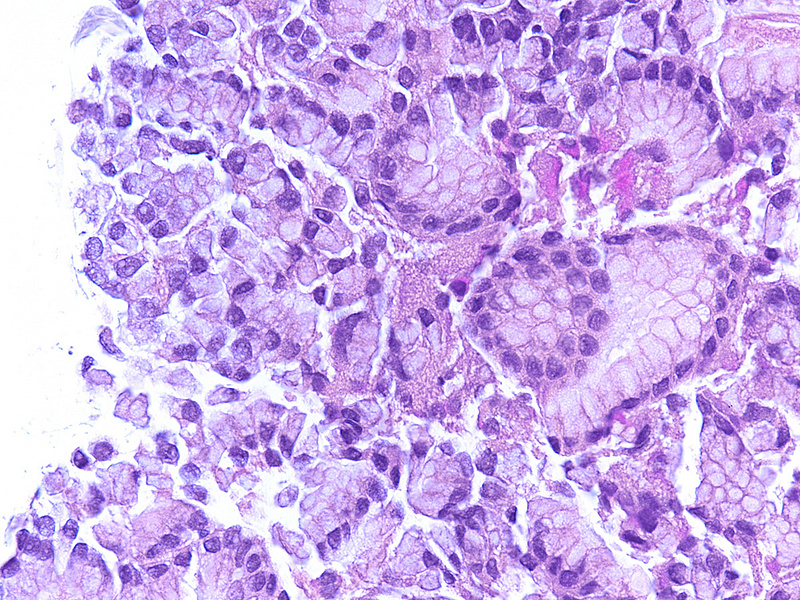

Gastric biopsy in a a 68 year-old female.

Pseudo signet ring cells (crush artifact).

A 68 year-old female underwent gastroscopy for mild epigastric discomfort.  The endoscopic findings were unremarkable, and routine biopsies were taken. On histology, within the corpus there were groups of sloughed, haphazardly arranged mucus neck cells at the mucosal surface that displayed centrally placed intracellular mucous vacuoles and eccentric nuclei. There was no visible nuclear enlargement or hyperchromasia (Panels A and B).

Mucus secreting cells located in the gastric pit neck region of fundic-type mucosa (mucus neck cells) represent the mucosal stem cell niche. When these cells become sloughed, dispersed, or crushed as result of manipulation, they may raise concern for signet ring cell adenocarcinoma. This finding represents a potential diagnostic pitfall that may result in dire consequences for the patient, as well as medicolegal consequences for the reporting pathologist. In contrast to signet ring cell adenocarcinoma, the nuclear contours of mucus neck cells are uniform and smooth, while the chromatin is of fine structure. No mitotic figures are seen. Unfortunately, as cytokeratin and PAS are both positive in mucus neck cells, they cannot aid in the distinction from adenocarcinoma and the diagnosis relies solely upon H&E morphology and awareness of this phenomenon. Besides cytomorphology, another helpful feature is the fact that mucus neck cells are in fact never dislodged within the lamina propria, but always in some sort of crease at the surface or at foci where the surface epithelium is artificially discontinued (admittedly, it may be slightly hard to assess this in certain cases).